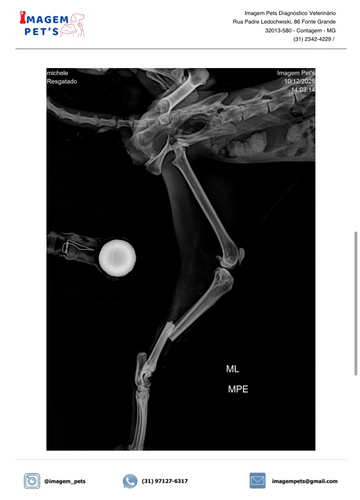

Olá pessoal! Hoje venho pedir a ajuda de vocês para mudar o destino da minha gatinha recém resgatada. Ela foi encontrada em situação muito delicada: extremamente desidratada, com múltiplas fraturas e sem forças para continuar lutando sozinha.

Mesmo diante de tanta dor, ela ainda encontra coragem para miar baixinho e pedir carinho. Nós não podíamos virar as costas! Ela já está recebendo atendimento, mas os custos com exames, internação, medicamentos e cirurgia são além do que posso pagar, e precisamos unir forças para garantir o tratamento completo e uma recuperação digna.